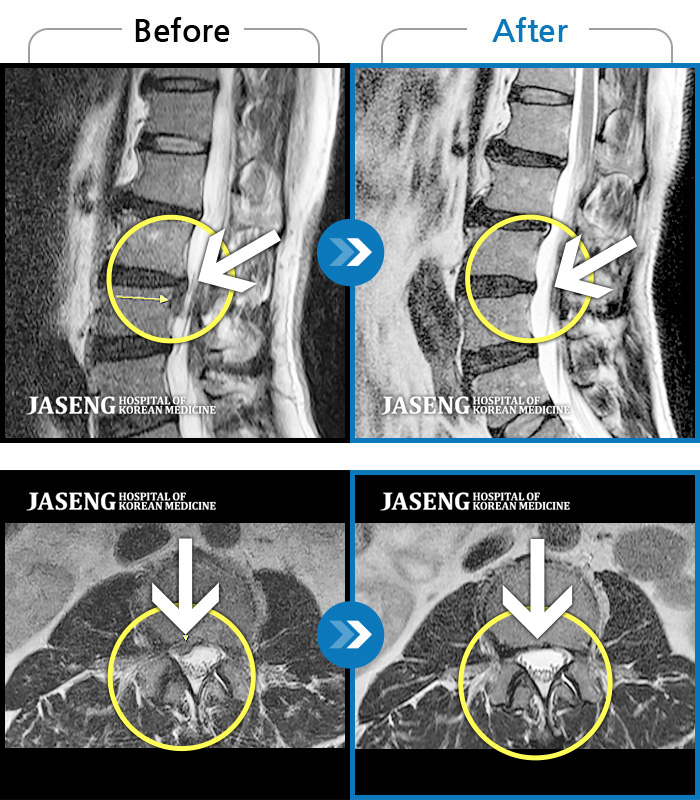

허리디스크

도움받은 사례

강남 · 강만호 원장

허리통증이 심해서 숙이기 어렵고 차에서 내리기 힘들었습니다.

촬영시기

2021.01.06 ~ 2025.03.10

2025.03.20